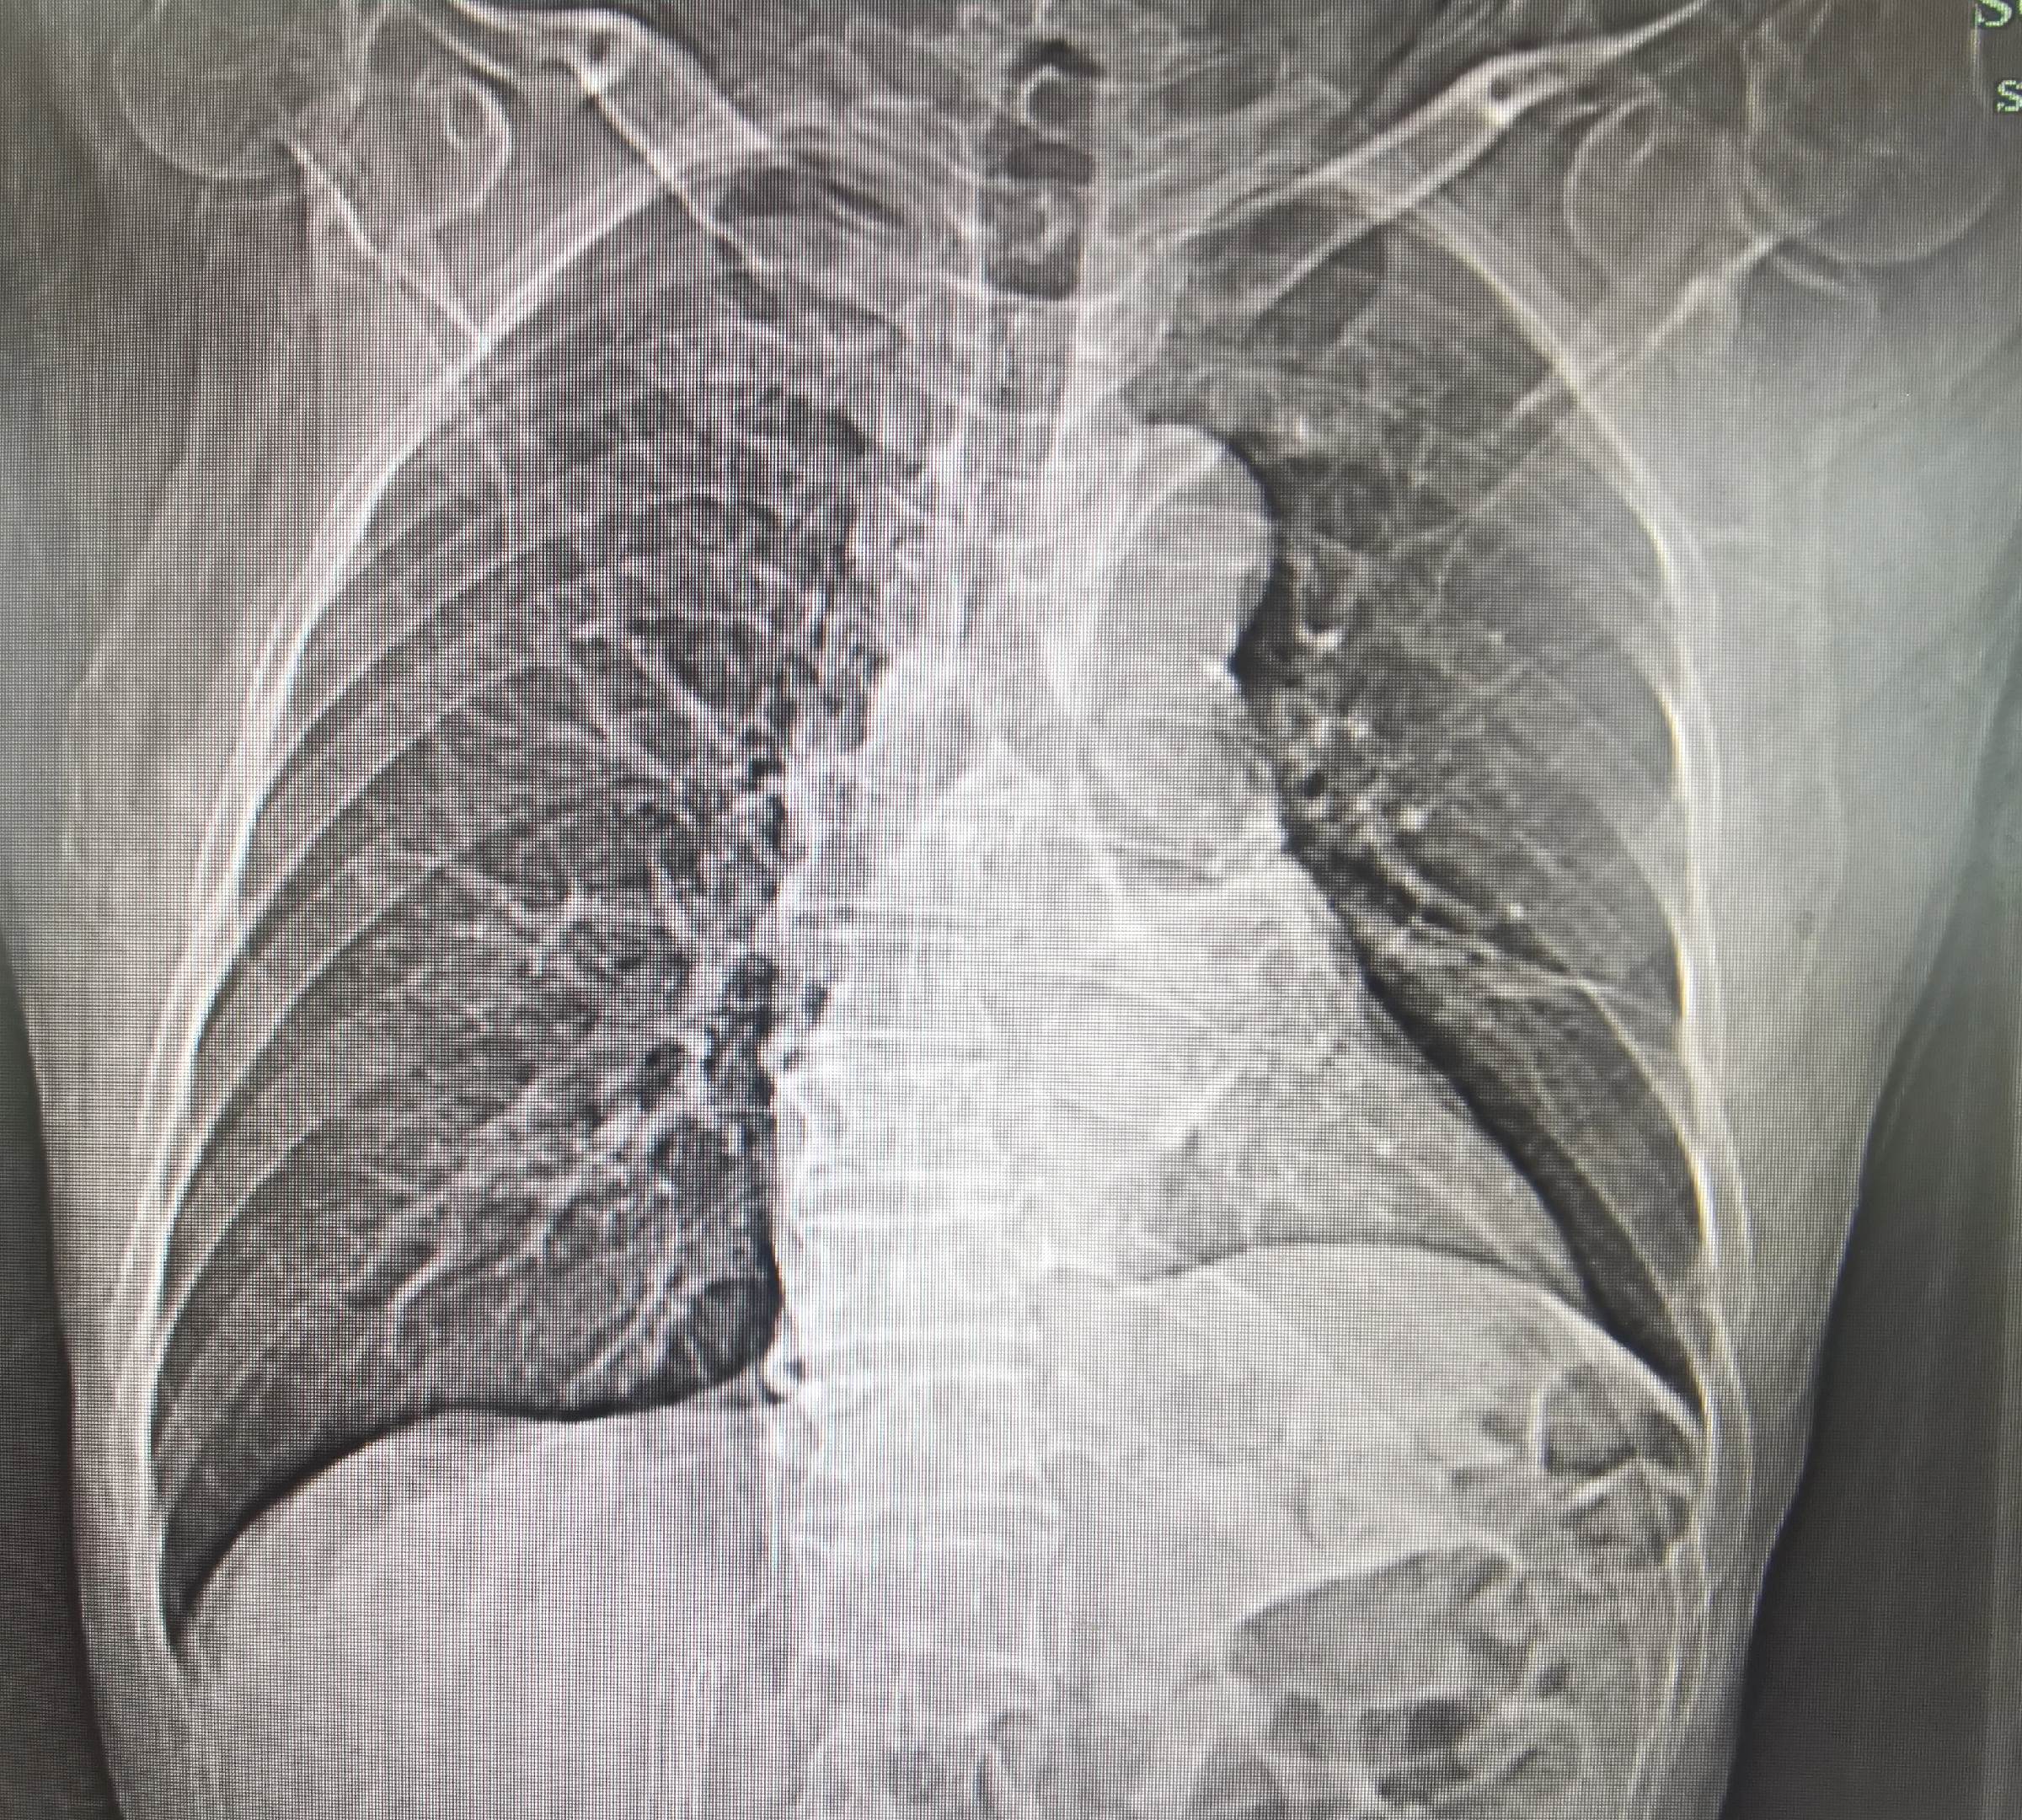

肺癌患者,左肺完全肺不张。经过一次bace的治疗,一个月后复查CT左肺完全复张,为后续全身治疗提供条件